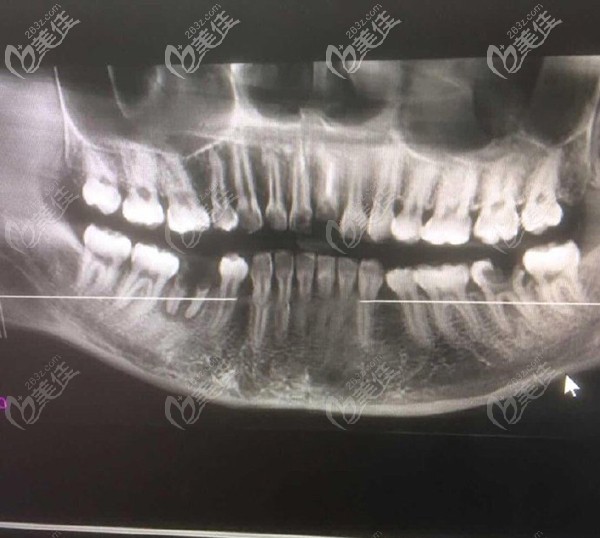

问题是本宝宝还不止缺一颗牙,只不过在我看来门牙尤为重要,来院后,医生大概看了牙齿情况后,建议还是拍个CT看看,以便于确认给我更好的方案。

放大看看更清楚

【牙齿情况】:门牙缺失一颗,下半口缺失一颗,但是有残根。